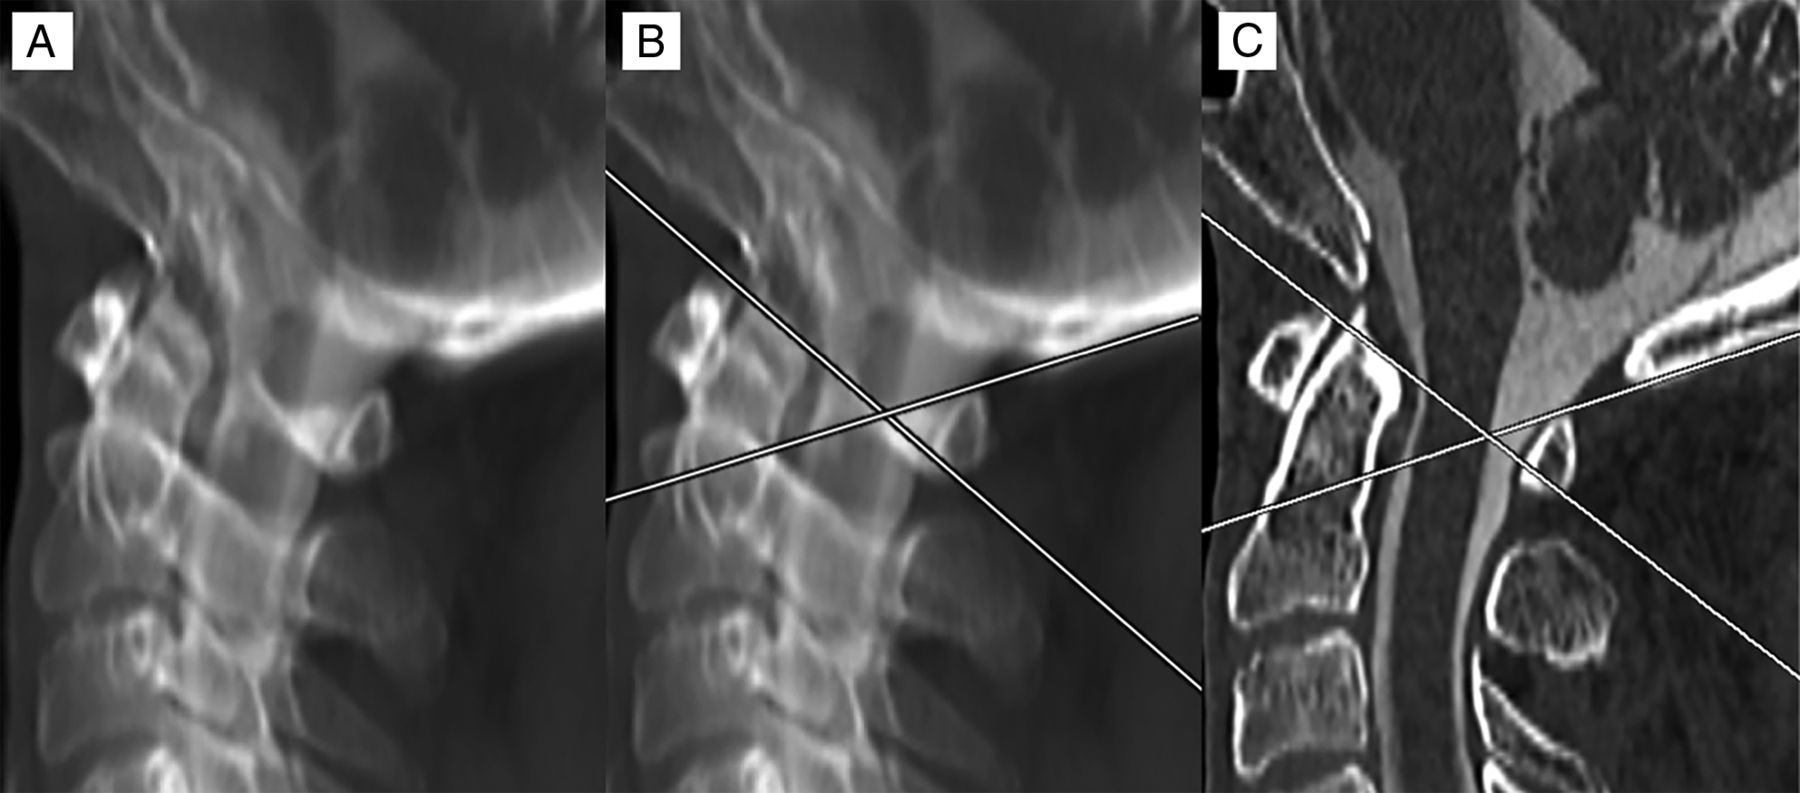

Method of measurement for the C1 posterior arch FP. An MIP image was created of a high-resolution sagittal reformatted cervical CT myelogram. Alignment adjustments were performed to overlap the bilateral posterior arches (A). Lines were drawn tangential to the superior cortex of the anterolateral and posterior arches. Where these lines overlapped was considered the FP (B). The MIP was then converted back to a 1-mm-thick section to evaluate the position of the FP from the dorsal spinal cord, which, in this case, showed direct correspondence, measuring 0 mm (C).

The relative location of the C1 posterior arch triangular FP to the dorsal spinal cord border was determined in all cases by the following methods: 1) A maximum-intensity-projection image was generated for each cervical myelogram using sagittal reformats of high-resolution (1-mm-thick) axial images. An MIP thickness of 3.5 cm was used to simulate the appearance of the C1 arch projecting over the spinal canal on a lateral fluoroscopic view, with alignment adjustments performed to ensure that the bilateral posterior arches precisely overlapped. 2) Two lines were drawn to approximate the angle of the anterolateral and posterior arches—the first line tangential to the superior cortex of the anterolateral arch and the second line tangential to the superior cortex of the posterior arch. 3) The FP apex was determined at the point where these lines intersected. 4) The distance of the FP apex to the dorsal margin of the spinal cord was measured. If this line was anterior to the cord, negative measurement values were used, and if the line was posterior to the cord, positive measurement values were used (Fig 2). Measurements were performed by a neuroradiology fellow and neuroradiology attending physician.